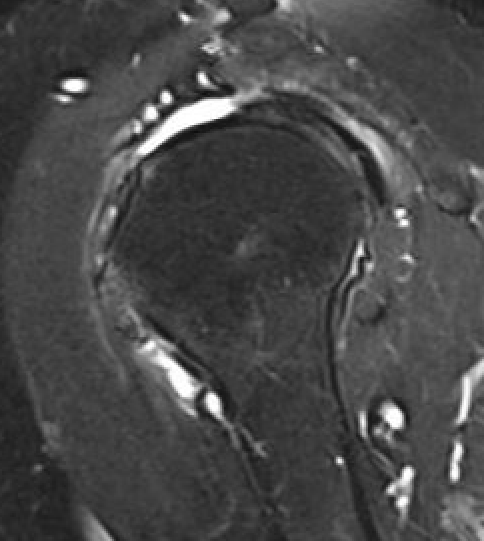

Partial bursal sided tear Partial articular sided tears

Subscapularis tears

Supraspinatus atrophy

Tangent sign

- sagittal MRI

- line connecting superior coracoid and superior border scapular spine

- if supraspinatus muscle is below line, there is significant atrophy

- positive tangent sign / significant atrophy associated with larger tears / irrepairable tears

Negative tangent / no atrophy Positive tangent / significant supraspinatus atrophy